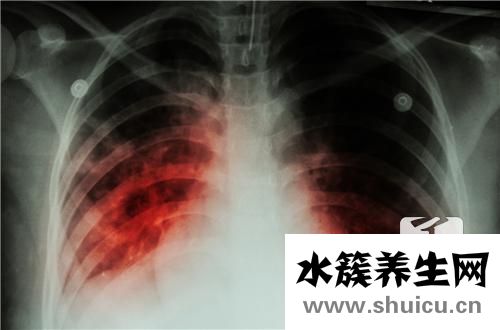

?眾所周知,結核分枝桿菌是一種具有較高感染率的病毒。 例如,結核病是生活中的常見疾病,是由結核分枝桿菌引起的疾病。 在協助存在結核感染的患者的過程中,結核皮膚檢查已成為非常重要的輔助方法,那么結核皮膚檢查如何看待結果呢?

結核菌素試驗也叫“OT”試驗,是判斷有無結核病的一種早期輔助診斷方法。當結核菌進入人體后,經四至八周機體產生對結核菌的過敏反應。此時做結核菌素試驗就出現陽性反應。目前國內通用皮內注射法,具體作法是:用1:2000稀釋液0.1毫升(5單位)注入前臂掌側中、下1/3交界處皮內,使之為直徑6~10毫米的皮丘。

利用結核菌素在人體皮膚上進行試驗,可以判斷受試者是否感染過結核桿菌。試驗結果報告的意義主要為:

1、結核菌素試驗陽性,表示受試者曾經受到過結核菌感染或已經接種過卡介苗,但不能判定其是否患有結核病。

2、結核菌素試驗強陽性,表示體內有活動性結核菌。

3、對于3歲以下,特別是1歲以下尚未接種過卡介苗的小兒,如果結核菌素試驗陽性反應,則表示體內有新的結核病灶。年齡越小,患活動性結核的可能性越大。

4、如果兩年之內結核菌素皮試結果由陰性轉為陽性,或反應強度從原來的硬結直徑小于10毫米增至大于10毫米,提示新近感染過結核菌,或可能存在活動性病灶。

5、結核菌素試驗陰性,表示受試者未受到過結核菌感染,也未接種過卡介苗,或接種未成功。

6、應該注意的是,某些情況下同樣會引起結核菌素試驗呈現陰性反應;如當機體免疫功能低下或受抑制時,(如嚴重營養不良、重癥結核等),可呈假陰性反應。